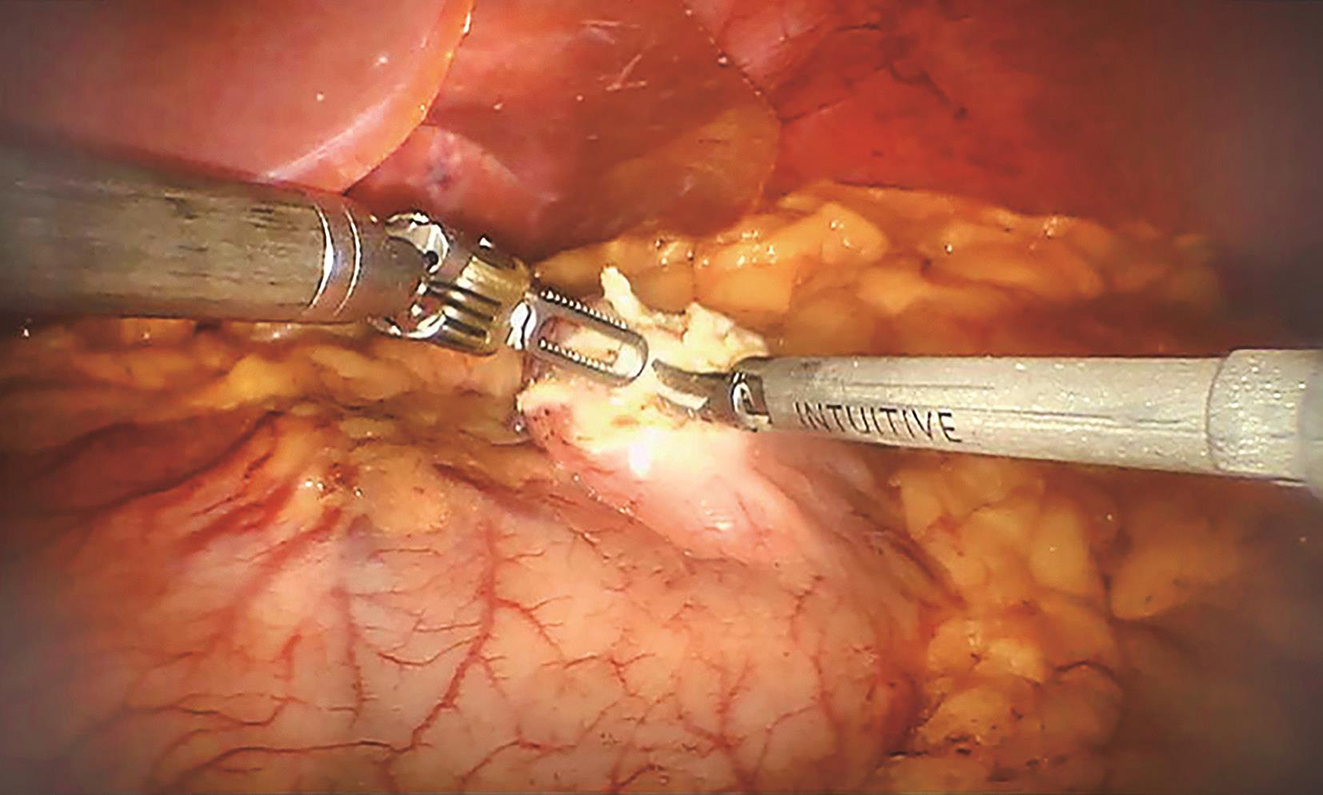

患者于加速康复外科(enhanced recovery after surgery,ERAS)理念指导下行术前准备,2016年9月27日行“机器人辅助下腹腔探查术+胃肿瘤切除术”。术中先行胃镜探查发现肿瘤位于胃底后壁近贲门处,大小约2.0cm×1.0cm;离断大弯侧网膜,暴露胃后壁瘤体,切开后壁肿瘤所对应胃前壁,以腹腔镜下切割吻合器于距离瘤体1cm处离断胃壁,完整切除肿瘤,将肿瘤置入标本袋中并用丝线结扎袋口,经绕脐半周切口取出,检查标本切缘安全,以可吸收线加固切口,缝合腹部戳孔及绕脐切口。手术过程顺利,手术时间60min,术中出血量约为10ml(图2~图5)。

图2 切开胃前壁